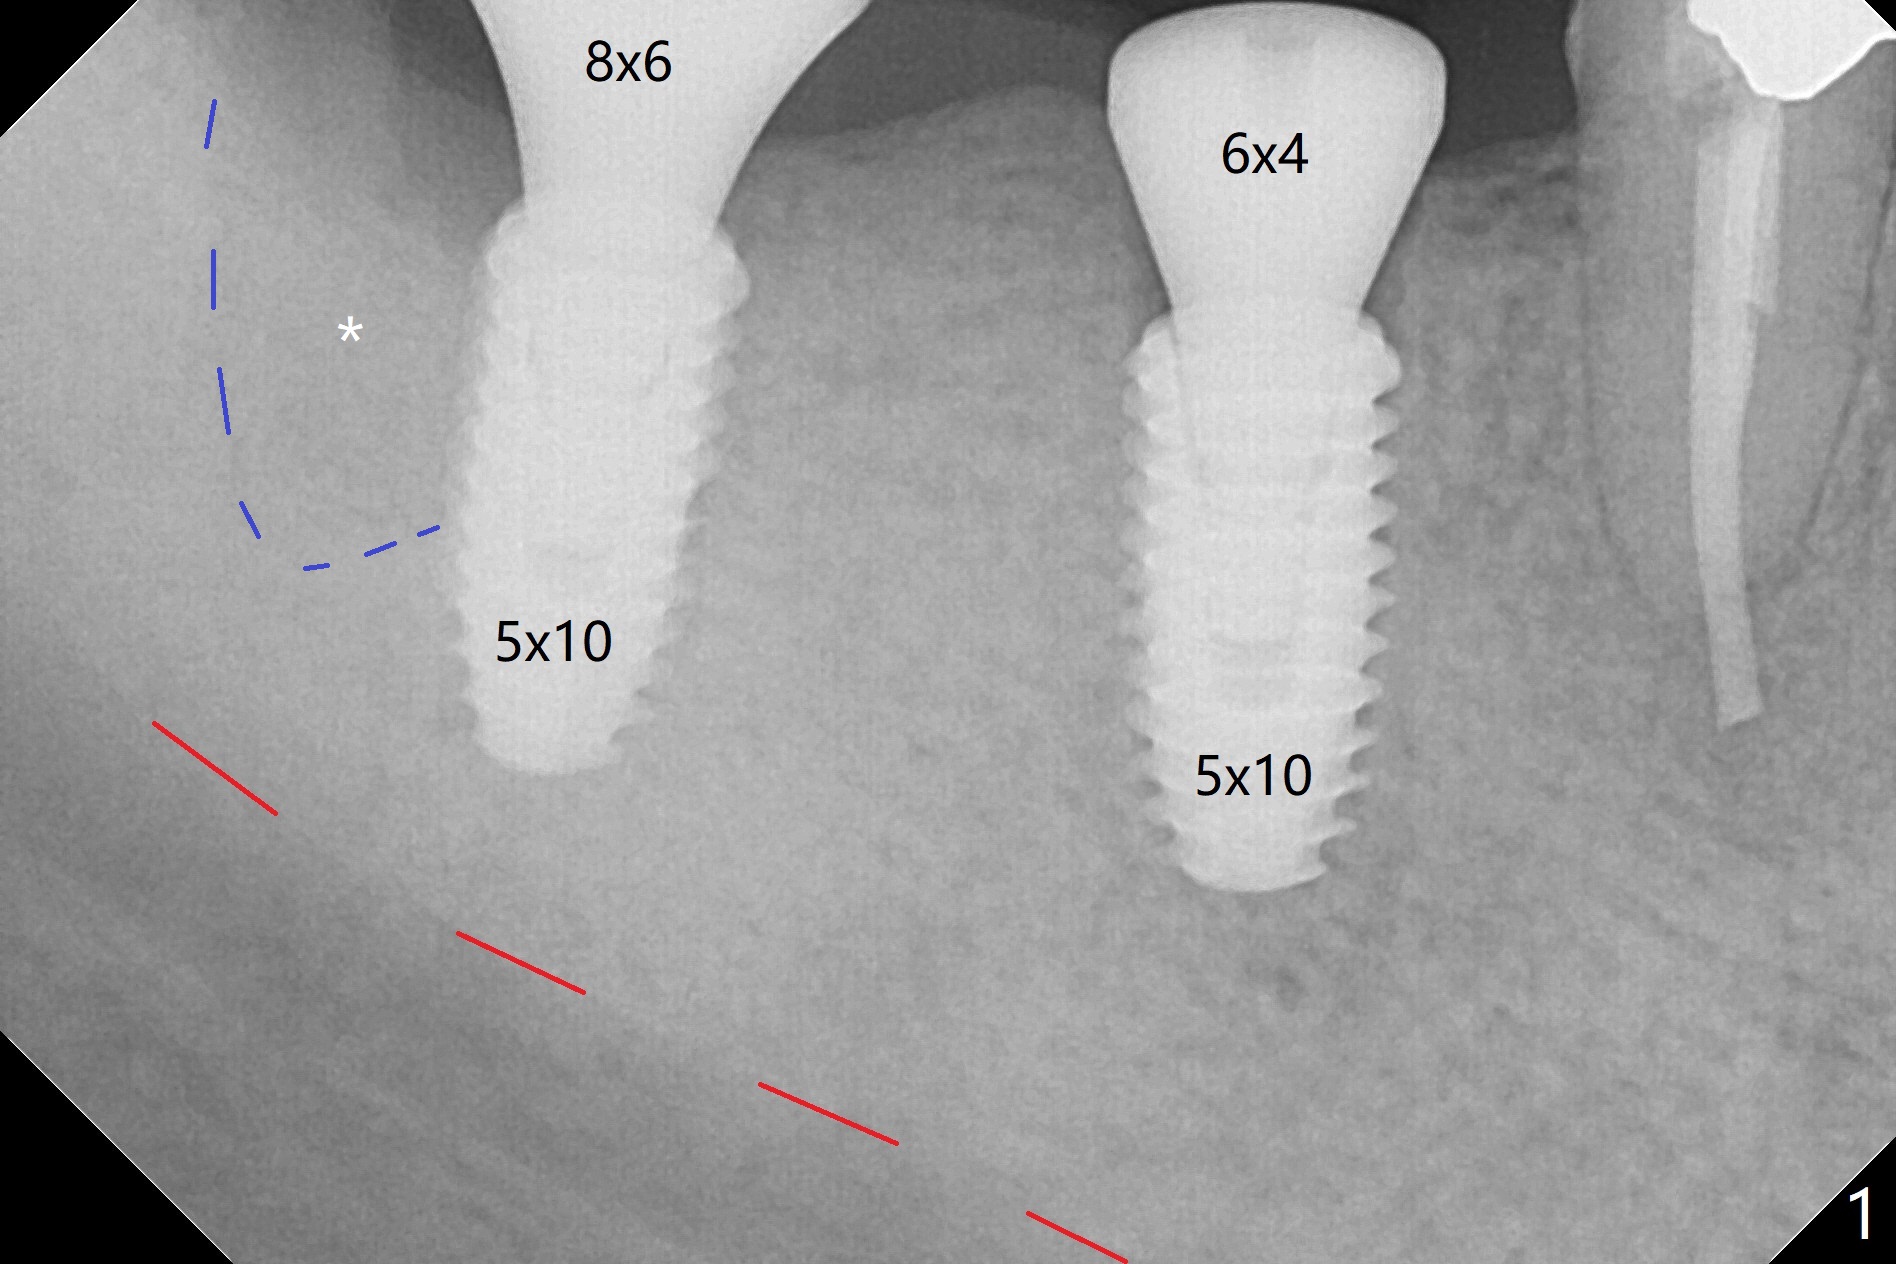

The bone at #30 and 31 is so hard that plenty of bone shaving is saved as bone graft to be placed in the socket of #31 post implantation (Fig.1,2 * (blue dashed line: #31 socket)). The guide is long and stable, allowing osteotomy without use of an anchor pin. Since the vertical space is limited, no provisional is fabricated. The bone graft is kept in place with collagen plug on the top and suturing. No provisional is fabricated because of limited vertical space (Fig.2). It appears necessary to intrude #2 and 3, which seems difficult since the patient is a bruxer (hard bone). The implants are placed as planned because of metal tubes (Fig.3). The patient develops postop pain, which is relieved by taking 800-1000 mg Ibuprofen every night. Exam shows mild percussion at the tooth #29 with gutta percha extrusion and periapical radiolucency (Fig.1,3). An endodontist refuses #29 RCT retreatment. What should be done?